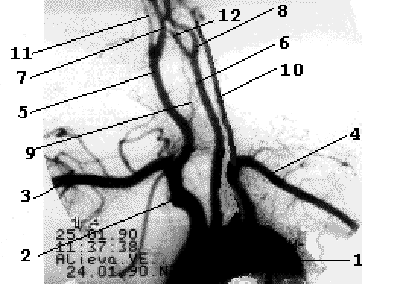

Рис 1.3 Рентгеноанатомия

брахиоцефальных ветвей дуги аорты. Наружная сонная артерия имеет короткий ствол, делясь на ряд ветвей, что легко позволяет отличить ее от ВСА. Насчитывают девять ветвей НСА, ряд из которых (терминальные ветви лицевой, поверхностной височной и верхнечелюстной артерий) анастомозируют с конечными ветвями глазничной артерии (первая интракраниальная ветвь ВСА) (Рис 1.4).